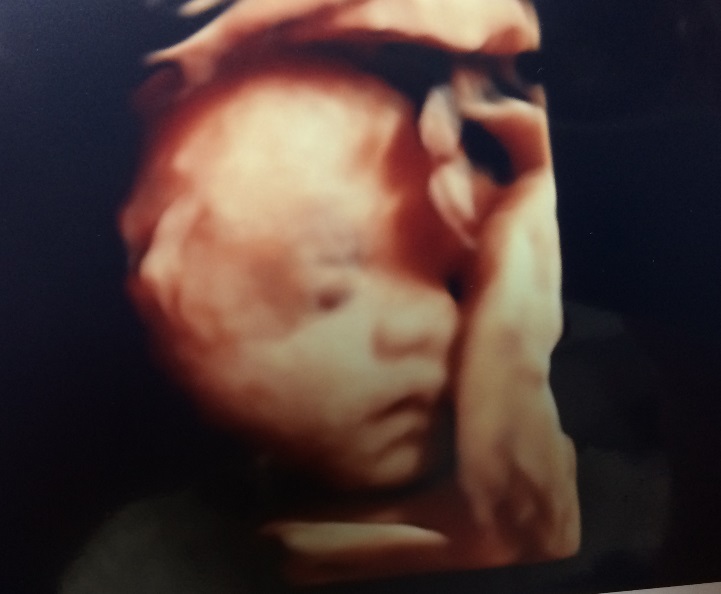

妻も妊娠29週目になりました。

エコー健診では、3Dでだいぶ輪郭が鮮明に…

夫婦二人して、エコー写真見ながら

北斗の拳(ケンシロウ)みたいだね…

と劇画調になってきた凛々しい娘(予定)の顔を眺めてました ^_^;

「可愛らしい」より「カッコいい」感じになってきたので、妻が心配になっています。

口唇は完全に妻似ですね。